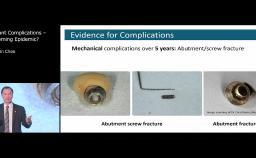

In this lecture Dr. Buser describes the most common causes of esthetic implant failures, in particular how malpositioning of the implant affects esthetic outcomes and which kind of mistakes are commonly made. Most such cases require implant removal, which results in creation of a bone defect and, very often, a soft tissue defect, i.e., lack of keratinized mucosa. He describes techniques of implant removal, methods to reestablish keratinized tissue, and factors which determine sequence of procedures needed to improve the outcome.

describe causes of esthetic implant failures

define treatment options for correction of esthetic failures